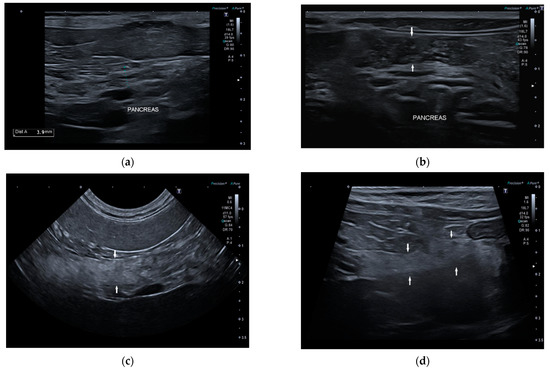

Conversely, 7/22 dogs (32%) had one or more of the anomalies described: two dogs had multiple hyperechoic spots in pancreatic parenchyma; one dog had inhomogeneous pancreatic echotexture with multiple hyperechoic spots; one dog had diffuse hyperechoic parenchyma with inhomogeneous echotexture and tortuous pancreatic duct; one dog had irregular margins and shape, hyperechoic parenchyma, and inhomogeneous echotexture; one dog had diffuse pancreatic heterogenicity, and one dog had irregular margins and tortuous pancreatic duct (Figure 3). The age of onset of symptoms in six of these seven dogs with abnormal parenchyma was greater than 4 years.

Figure 3.

Ultrasound image of right pancreatic limb: (a) Pancreas (between the caliper) with regular margin, homogeneous echogenicity, and mild inhomogeneous echotexture (b) Pancreas (between the white arrows) with regular margins (thickness 6.5 mm), normal echogenicity, and multiple point mineralizations (c) Pancreas (between the white arrows) with irregular margins (thickness 5 mm) multifocal hyperechogenicity, and inhomogeneous echotexture (d) Pancreas (between the white arrows) with irregular margin (thickness 4 mm), diffuse and severe parenchymal hyperechogenicity, and inhomogeneous echotexture.